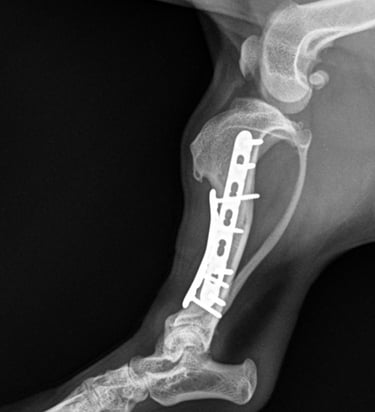

Postoperative radiographs confirmed excellent implant positioning, appropriate fracture alignment, and good apposition of fracture ends (Fig. 3 and 4).

At the 6-week postoperative recheck, radiographs showed good progression of fracture healing with maintained alignment and implant integrity (Fig. 5 and 6).

Fig. 4

Fig. 6

Fig. 5